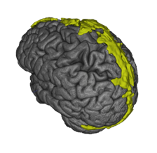

Quantitative Volumetry

Measuring the volume and appearance of brain and spinal cord structures can yield important insights about the health of the underlying tissue. Abnormal shrinkage of certain brain areas early in the course of multiple sclerosis (MS) can herald clinical decline. For example, the thalamus is one of the earliest structures to shrink in MS and we collaborate with the Saranathan Lab in assessing thalamic subnuclear segmentation. We employ a wide variety of tools to accurately quantify brain structures. Among many, these can include Freesurfer, FSL, SPM, C3D, ITK-SNAP, 3D Slicer, and ANTs. We are now implementing newer deep learning segmentation tools that can be trained on relatively small datasets as well. The Principal Investigator (PI) runs a longitudinal, observational study of MS (the OPTIMUM study) to study real-world information from persons with MS, a resource that allows new insights into the disease by combining MRI with clinical data informatics.